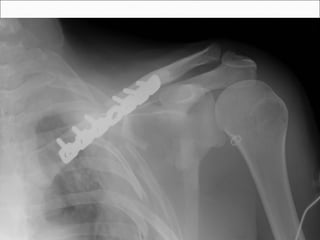

Plate Fixation

 Traditional means of ORIF

 Plate applied superiorly or inferiorly

 Inferior plating associated with lower risk of hardware

prominence

 Used for acute displaced fractures and nonunions.